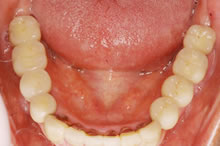

- 【術後】

- 左右の奥歯に最終の被せ物が入った状態です。

前歯も治療し、全体的に噛みあわせが安定性しました。